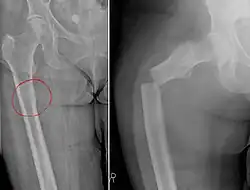

Chalkstick fracture due to bone metastasis of breast cancer. The left image shows the metastasis, on the right a pathological fracture a few days later.

Chalkstick fractures are fractures, typically of long bones, in which the fracture is transverse to the long axis of the bone, like a broken stick of chalk.[1] A healthy long bone typically breaks like a hard woody stick as the collagen in the matrix adds remarkable flexibility to the mineral and the energy can run up and down the growth rings of bone. The bones of children will even follow a greenstick fracture pattern.